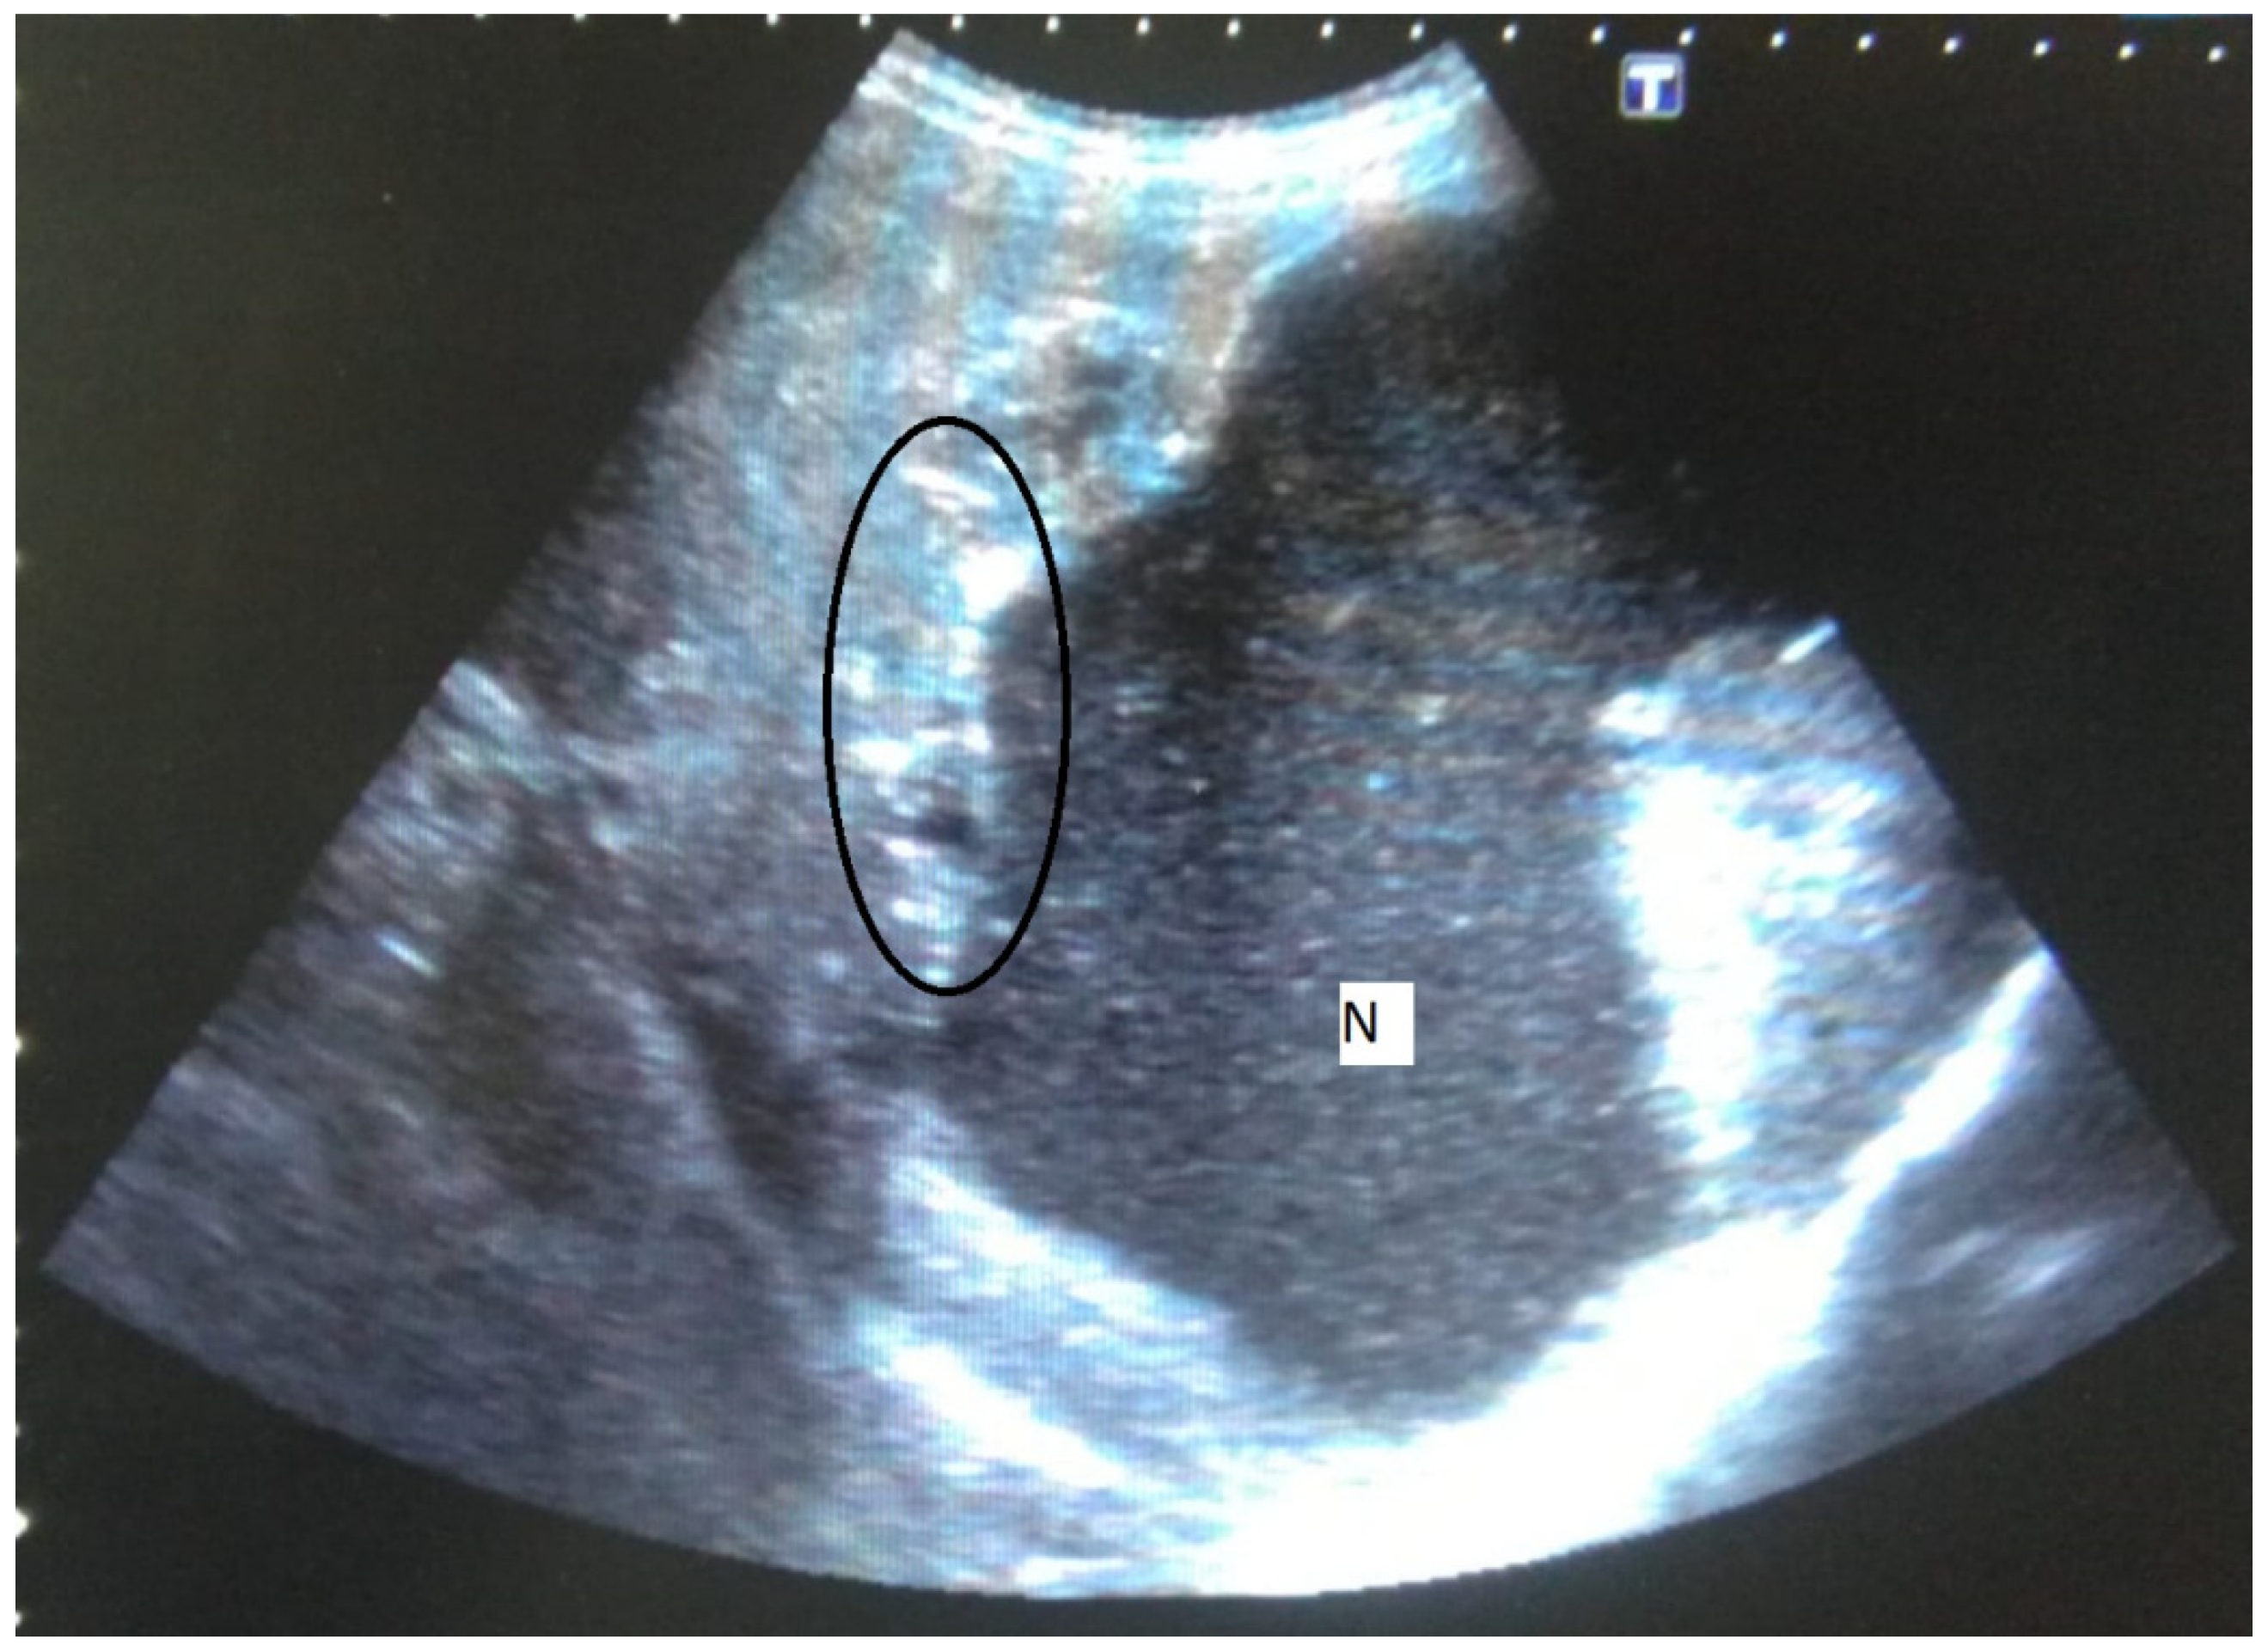

A mass lesion with a mixed heterogeneous echogenic pattern and irregular contours, including cystic necrotic areas and multiple distributed calcific foci, was the most common sonographic appearance (73.1%) (Figure 1). Table 2 shows the distribution of sonographic appearances in great detail. Color Doppler ultrasonography (CDUS) revealed no vascularization in any of the lesions.

Figure 1.

58-year-old female. Hepatic lesion with irregular margins, calcifications (circle), and large cystic-necrotic component (N) are seen.